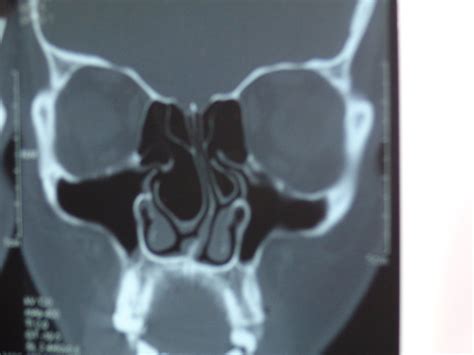

When an air cell develops within the middle turbinate, the structure expands significantly. This expansion is the defining characteristic of a Concha Bullosa. Depending on the size of the air pocket, the enlarged turbinate can press against the nasal septum or the lateral nasal wall, effectively narrowing the nasal passage and obstructing the narrow drainage pathways, known as the ostiomeatal complex, where the sinuses drain into the nose.

Diagnosing a Concha Bullosa typically requires more than a simple visual inspection during a physical exam. While an ENT might suspect the condition using an endoscope—a thin, flexible tube with a camera—a definitive diagnosis almost always relies on imaging. A Computed Tomography (CT) scan of the paranasal sinuses is the gold standard. It provides a detailed cross-sectional view of the nasal architecture, allowing the physician to measure the exact size of the air pocket and determine if it is contributing to sinus obstruction.

CT Scan Detailed imaging to confirm pneumatization and identify potential obstruction sites.